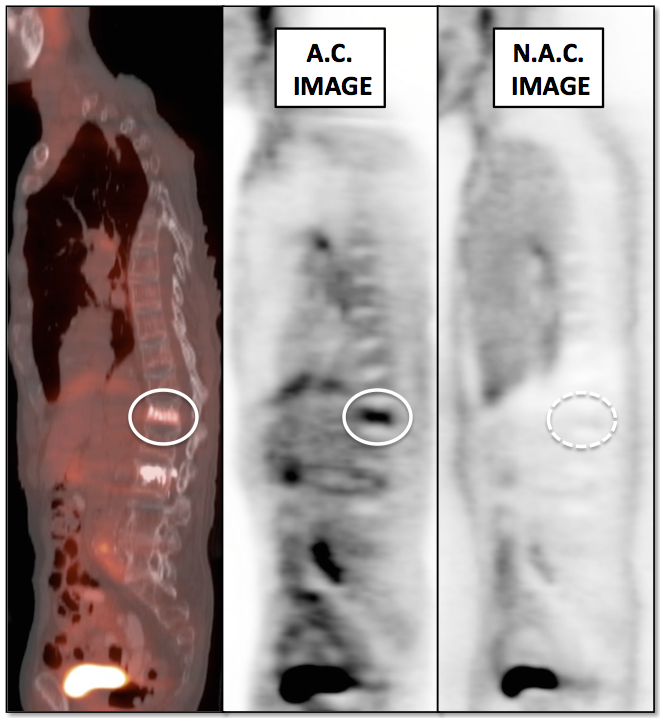

Value of Non-Attenuation Corrected (NAC) Images

Resolving Attenuation Correction Artifacts:

The CT images obtained during an exam are not only used for “anatomic” interpretation. They are also used for “attenuation correction” (AC) of the PET images, generating the much more useful AC PET images used for interpretation.

Unfortunately, attenuation correction of PET images can result in falsely elevated metabolic activity in regions of high CT density (e.g. metallic devices, oral contrast, calcification).

In such cases, these areas must be reviewed on the NAC (non-attenuation correction) images. If these regions are not also hypermetabolic on the NAC images, then their apparent increased FDG-uptake on the AC images is artefactual.

This phenomenon is almost exclusively seen with older PET/CT scanners, as most modern scanners utilize newer algorithms that do not “over-correct” in these areas of increased density.